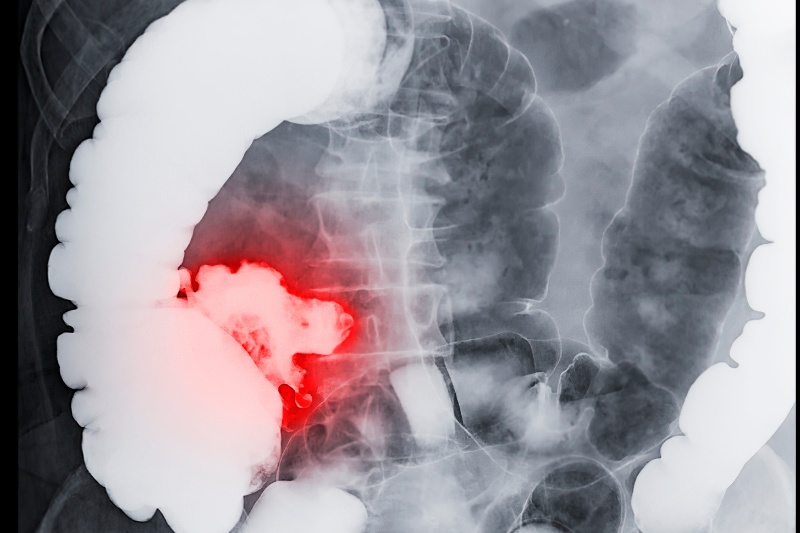

Ung thư đại trực tràng

Ung thư đại trực tràng cũng chính là 1 trong 7 loại ung thư có khả năng chữa khỏi. Đây là một loại ung thư phát triển từ tế bào trong thành trực tràng, một phần của hệ tiêu hóa. Đây là loại ung thư phổ biến thứ hai ở nam giới và thứ ba ở nữ giới trên toàn cầu. Triệu chứng của căn bệnh này có thể bao gồm thay đổi về thói quen đại tiện như tiêu chảy hoặc táo bón, đau bụng, khó tiêu hoặc cảm giác đầy bụng, mệt mỏi và giảm cân không rõ nguyên nhân. Tuy nhiên, trong nhiều trường hợp, không có triệu chứng rõ ràng trong giai đoạn sớm của ung thư đại trực tràng.

Theo thống kê của Tổ chức Y tế Thế giới (WHO), tỷ lệ sống sót của ung thư đại trực tràng trên toàn cầu là khoảng 65%. Tuy nhiên, tỷ lệ này có thể khác nhau tùy thuộc vào từng quốc gia hoặc khu vực. Nếu bệnh nhân được phát hiện và điều trị trong giai đoạn sớm, tỷ lệ sống sót của ung thư đại trực tràng có thể lên đến 90%. Tuy nhiên, nếu bệnh được phát hiện ở giai đoạn muộn, tỷ lệ này sẽ giảm xuống, khoảng từ 10 đến 15%.